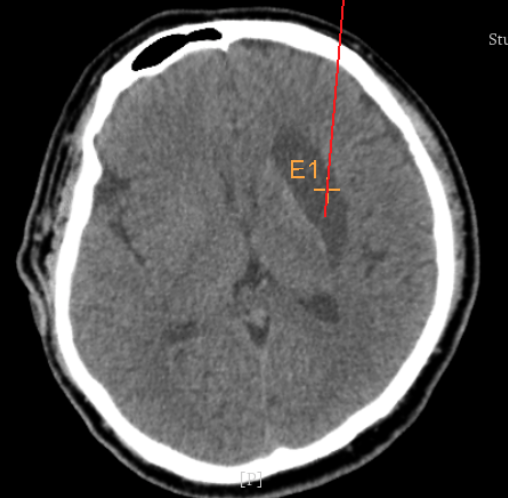

術(shù)前CT:血腫已經(jīng)液化,但仍有占位效應(yīng)